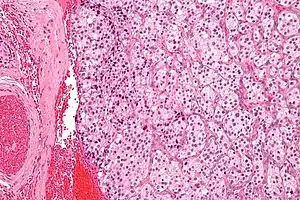

| ریزنگاری یک تومور جسم سباتی (نوعی از پاراگانگلیوما) | |